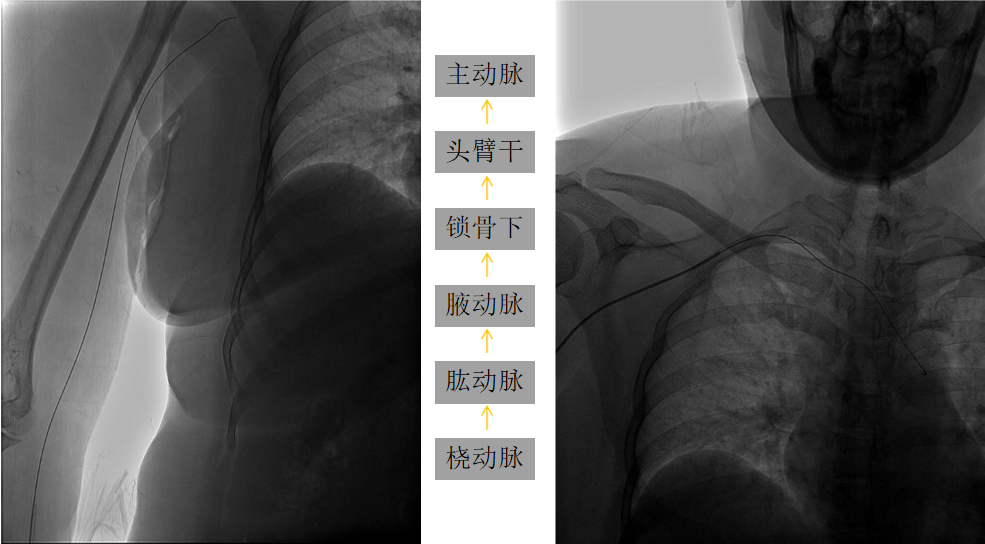

入弓:

泥鳅导丝辅助下,将Pigtail猪尾巴管送入升主动脉,行主动脉弓造影;完成造影后,放入泥鳅导丝把猪尾巴管撑直,然后将泥鳅导丝和猪尾巴管一同退出体外;也可以沿猪尾巴管放入0.35in 260cm交换导丝,保留导丝交换出猪尾巴管,再由SIM2管沿交换导丝放入主动脉弓;或此步骤用泥鳅导丝将SIM2管带入主动脉弓。

SIM2导管过弓要点

右侧为升主动脉,左侧为降主动脉;升主动脉部成袢易损伤主动脉瓣,可能致心律失常,慎用;通常 在降主动脉成袢;导丝进入降主动脉后,再部分推入SIM2导管,撤导丝,轻轻退并 顺时针旋转导管,成袢;对于3型弓,导丝过弓可能困难,建议导丝塑大弯,路图下过弓。